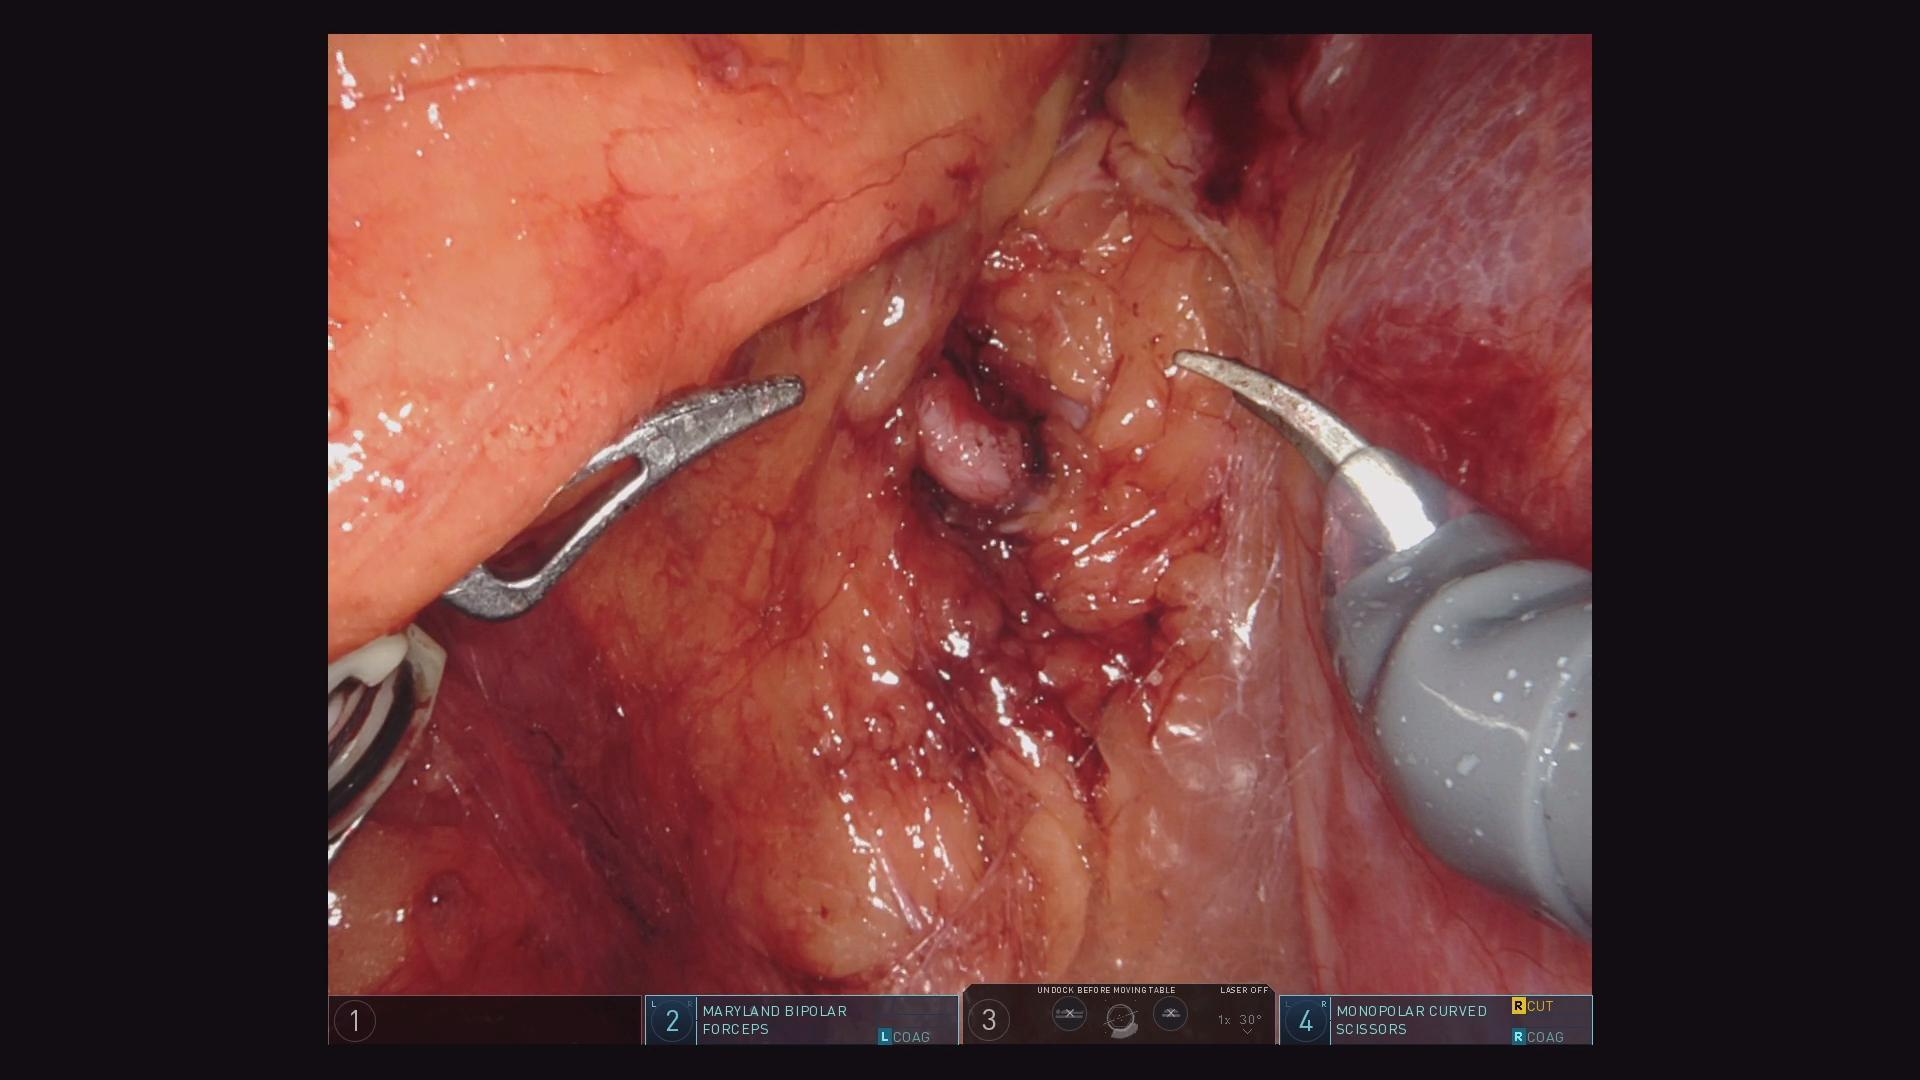

肾1.jpg

达芬奇机器人显露肾肿瘤

该病例为一右肾癌,外生性生长。我们团队采用机器人辅助下腹腔镜技术,入路选用腹膜后途径。我们医院是全国最早引入手术机器人的单位,目前已经更新迭代到最新一代机器人。机器人手术在泌尿外科已经广泛开展,机器人辅助腹腔镜手术在肾肿瘤方面的治疗疗效不断被验证。与传统开放手术和腹腔镜手术对比,机器人辅助腹腔镜手术疗效相当,且具有许多优势,尤其在肾肿瘤肾部分切除术的应用上。对手术者来说,腹腔镜手术技术要求较高,学习曲线长,而在这种复杂的重建和高级的切除手术中,机器人可为术者提供3D视觉、7个活动度的仿腕型器械、移动缩放和减少震颤。简化手术操作,缩短学习曲线。

常规来说,肾癌部分切术需要阻断肾动脉,这样会导致肾缺血,而且缺血时间越长肾功能受损越严重。我们团队充分利用达芬奇机器人的优势采用了零缺血创新术式,也就是不阻断肾动脉的情况下来做肾癌部分切除术。从后腹腔入路,借助于机器人手臂灵活的自由度,从肿瘤显露到切除、缝合肾脏一气呵成。同时切除肿瘤精准,减少了阳性切缘以及术后尿瘘的发生。